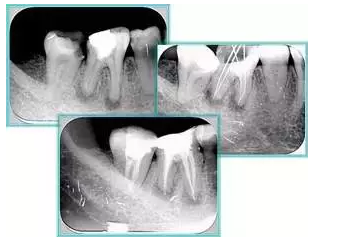

右圖及下圖為器械折斷的 X 線片。箭頭處示折斷器械。

右圖箭頭處示臺階形成。